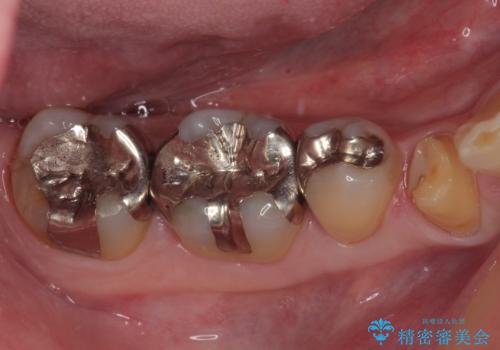

- 右下の銀歯が取れたとのことで来院された患者様です。以前にも取れていたところで、メタルインレーの不適合も認めていたため、次回外れたらオールセラミッククラウンにやり替えていくことを説明していたため、オールセラミッククラウンによる補綴治療を行っていくことにしました。

拡大鏡視野下で虫歯を除去しオールセラミッククラウンに適した形に整えました。